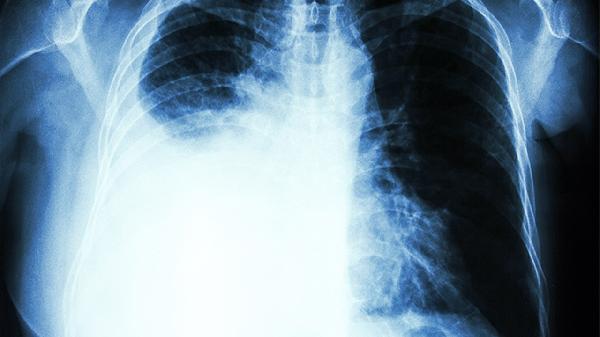

二、二级预防:在癌细胞觉醒前按下暂停键

年吸烟量≥30包的人群,每年低剂量螺旋CT检出早期肺癌的几率是胸片的4倍。但普通人群盲目做CT反而可能增加辐射风险。